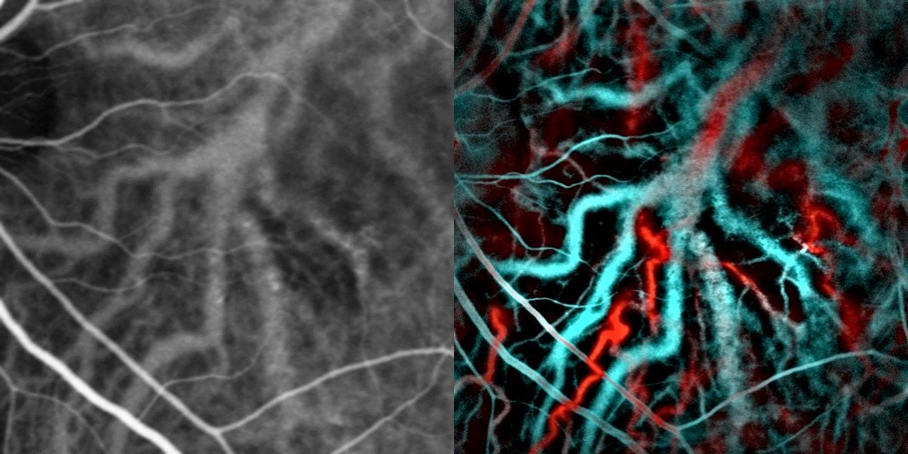

중심장액성망막병증에서 맥락막 혈관을 보여주는 인도시아닌 그린(왼쪽) 혈관조영술과 레이저 도플러 영상(오른쪽). 파란색과 빨간색은 각각 낮은 혈류와 높은 혈류에 해당한다.

인도시아닌 그린 혈관조영술 또는 레이저 도플러 영상을 사용하여 망막 색소 상피 아래의 부어 있는 기저 맥락막 혈관을 드러내고, 치료 결정을 내리는 데 유용할 수 있는 영향을 받은 부위의 망막 건강 상태를 평가할 수 있다.